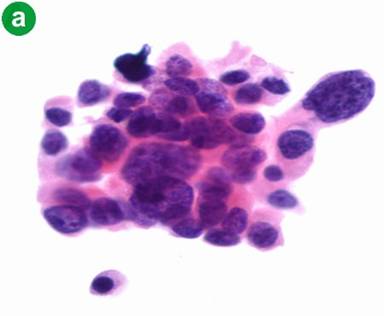

A 61-year-old female with history of hypertension, hyperthyroidism and depression presented with a one-day history of bilateral painless bluish discoloration of multiple toes. She was not on anticoagulants or any drugs known to induce vasospasm. She denied cocaine, tobacco or alcohol use. Family history was significant for colon cancer in her father. At admission, she was afebrile, with a blood pressure of 118/76 mmHg, a regular heart rate of 112 beats per minute and a respiratory rate of 22 per minute. Abdominal examination revealed hepatomegaly. She had bilateral bluish-black discoloration of multiple toes suggestive of a dry gangrene (Figure 1). The rest of her physical examination was unremarkable. New T-wave inversions in the inferolateral leads were revealed at electrocardiography. Initial blood tests demonstrated moderately elevated cardiac and liver enzymes (Table 1). Doppler study of lower extremities revealed bilateral thromboses of peroneal veins without any evidence of arterial occlusive disease. A transthoracic echocardiogram was normal. CT angiogram of chest and abdomen showed acute bilateral subsegmental pulmonary emboli and multiple hypodense hepatic lesions, along with a 3 cm mass arising in the pancreatic tail (Figure 2). This prompted therapeutic anticoagulation with unfractionated heparin. Over the course of the next 48 hours, she developed dysarthria, limb weakness and altered sensorium. A magnetic resonance angiogram of the head showed diffuse embolic infarctions with a large area of hemorrhagic transformation in the left temporal lobe (Figure 3). Extensive laboratory testing for an underlying hypercoagulable state was negative and serum CA 19-9 level was markedly elevated (Table 1). Fine needle aspiration biopsy from the liver lesions was consistent with metastatic adenocarcinoma (Figure 4). The diagnosis of metastatic pancreatic cancer was made based on the presence of a pancreatic mass, positive tumor markers and histopathology findings. Subsequently, the patient’s family opted for a transfer of care to a specialized oncology center, where she eventually expired several weeks later.

Figure 4. Hepatic fine-needle aspiration cytology demonstrating: a. malignant cells with marked anisonucleosis, nuclear membrane irregularity and cellular discohesion characteristic of a high grade adenocarcinoma; b. malignant ductal cells with expression of CA 19-9, suggestive of pancreatic primary adenocarcinoma. |